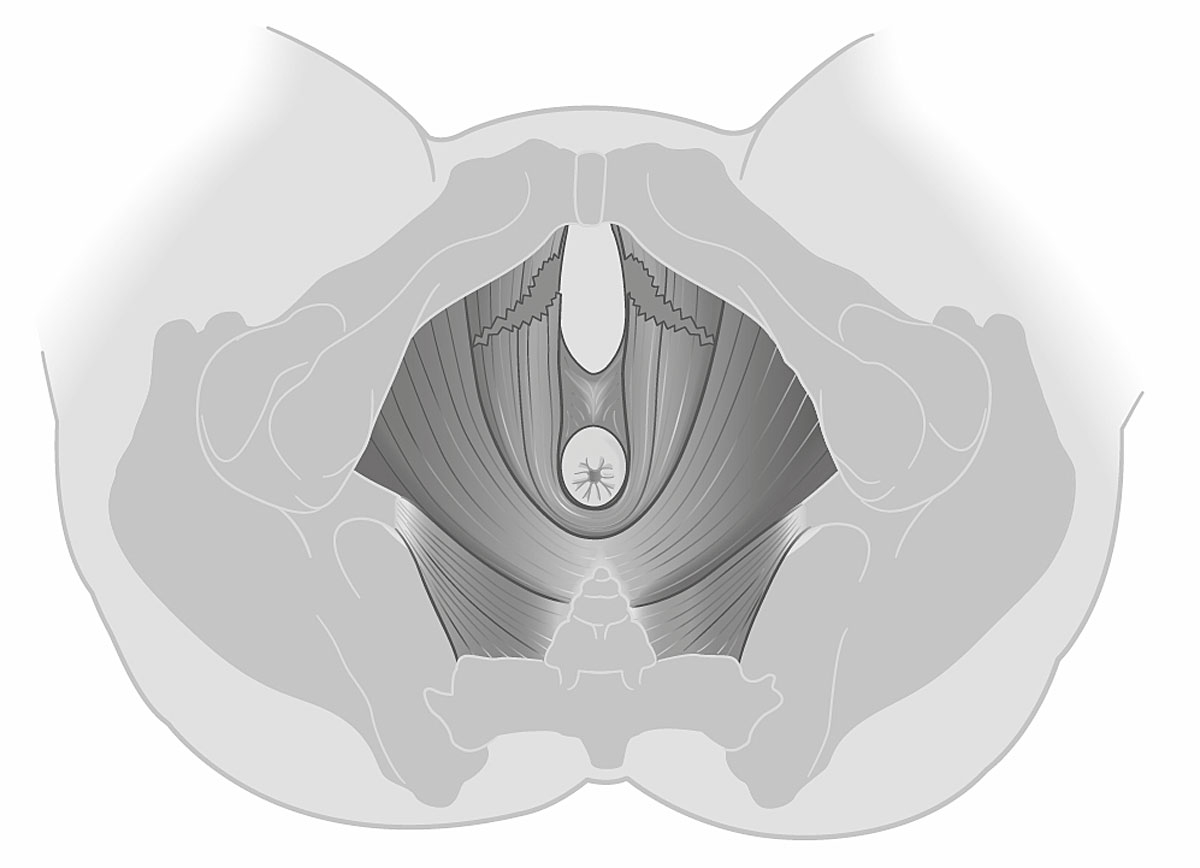

Of the 49 women with vacuum-assisted births in our cohort, 32 (65.3%) had an intact levator ani muscle, as shown in the illustration in fig. 2a and in the 3D ultrasound scan in fig. 2b. In contrast, 17 (34.7%) sustained levator ani muscle trauma, with 9 women (18.4%) having a partial levator ani muscle avulsion and 8 women (16.3%) having a complete levator ani muscle avulsion, as shown in the illustration in fig. 3a and in the 3D ultrasound scan in fig. 3b. No significant differences between the two groups were found, except for the state of their uterine contractions. Women without any levator ani muscle injury after vacuum extraction had more efficient uterine contractions compared to women with levator ani muscle trauma.

Figure 2a Illustration of an intact bilateral levator ani muscle.

Figure 3a Illustration of a complete bilateral levator ani muscle avulsion.